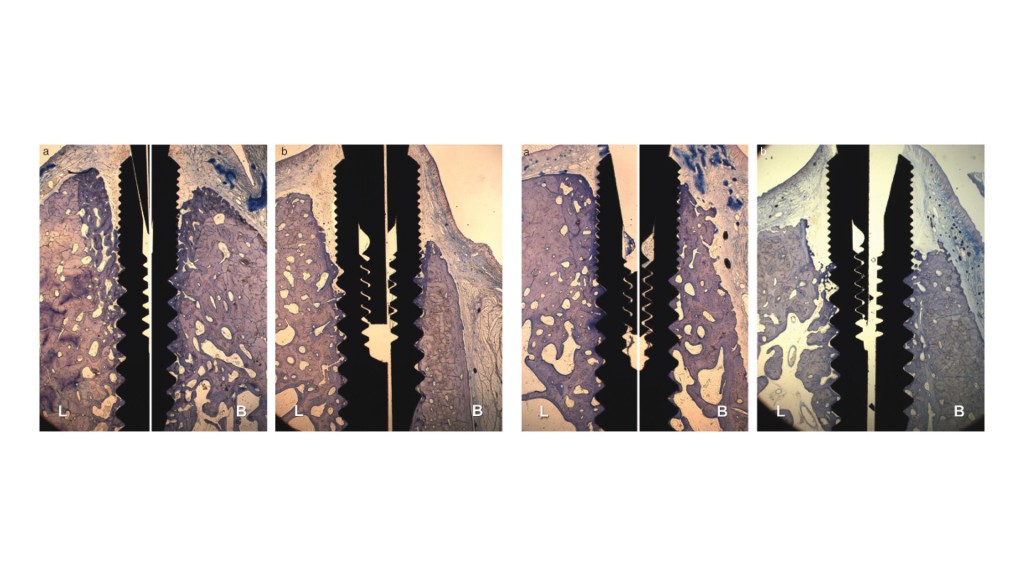

Guarda cosa ha dimostrato Botticelli nel 2006:

Le prime due immagini ti mostrano cosa a avviene a due mesi se metti un impianto in un “buco” artificiale fatto in osso guarito e in un alveolo post estrattivo; le ultime due ti mostrano la stessa cosa a quattro mesi. Come puoi vedere l’osso alveolare dopo l’estrazione si riassorbe esattamente come se non ci fosse l’impianto mentre nel caso del “buco” artificiale anche se viene scollato un lembo il riassorbimento è irrilevante!